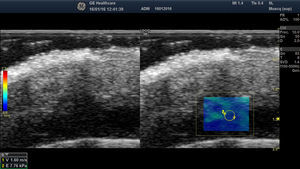

AdenopatíasEl objetivo de la evaluación de las adenopatías desde el punto de vista ecográfico es diagnosticar la afectación ganglionar de manera no invasiva en pacientes con lesiones clínicamente sospechosas de malignidad30.

Los ganglios linfáticos presentan una elastoestructura que suele presentar una cortical menos rígida que la cápsula y el hilio (fig. 6).

Para evaluar la rigidez de los ganglios linfáticos, la SE clasifica los ganglios en 4-5 grados en función de la proporción de áreas rígidas dentro del ganglio linfático31. Generalmente, las adenopatías benignas suelen ser blandas y las malignas suelen ser más duras32. Sin embargo, los linfomas presentan una dureza inferior a las adenopatías metastásicas y similar a la de las adenopatías inflamatorias, por lo que las adenopatías benignas y linfomatosas no pueden ser distinguidas aisladamente mediante elastografía33.

En el caso del melanoma (fig. 7), en el estudio de Hinz et al.34, la elastografía añadida al modo B y Doppler color permitió incrementar la sensibilidad en la detección de afectación ganglionar en adenopatías clínicamente sospechosas del 80,9% al 95,2%, sin incremento en la especificidad, que se mantuvo en el 76,2%. Estudios posteriores como el de Ogata et al.35 ofrecen resultados similares.